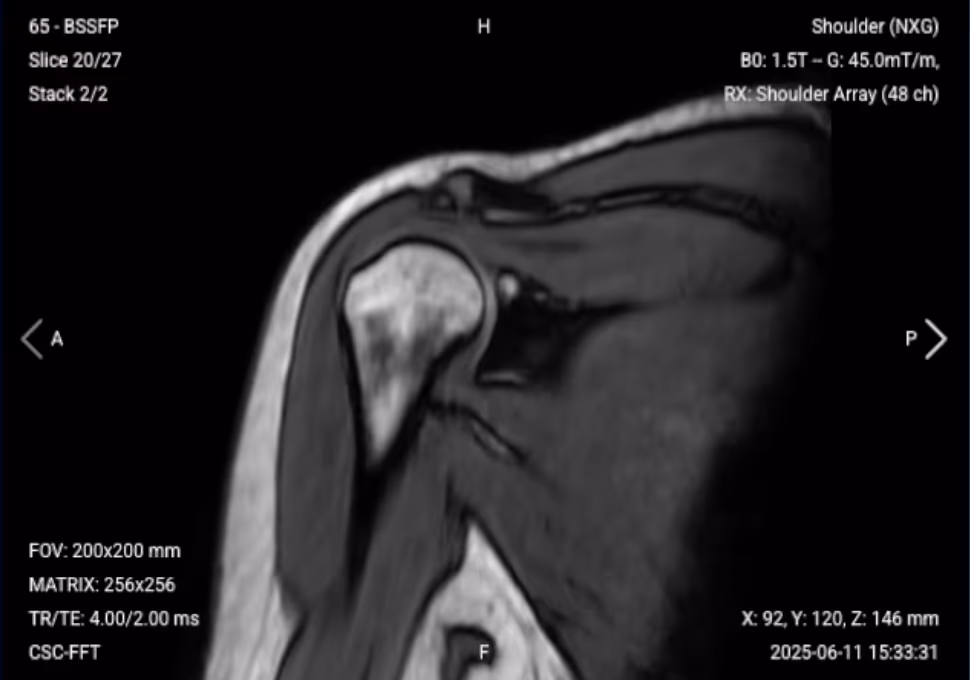

✅ Sagittal PD FS of the Shoulder – Correct Image Example:

Things to Look for in Sagittal PD FS:

✅ Coronal PD FS of the Shoulder – Correct Image Example:

Things to Look for in Coronal PD FS: